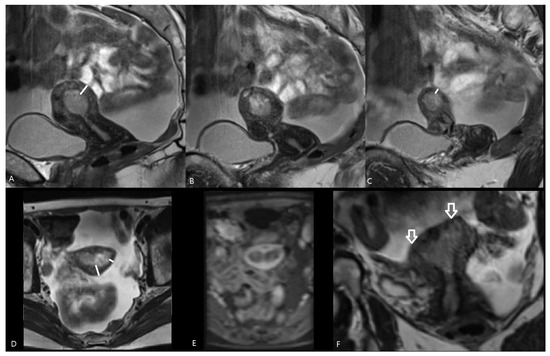

MRI has long been established as a valuable imaging method in the preoperative staging of EC. MRI can assess the depth of myometrial invasion, but histological type and grade can only be determined with endometrial tumor sampling (Figure 2). Preoperative staging with MRI may be advantageous to predict ≥pT1b disease preoperatively to avoid a second surgical procedure for lymphadenectomy [12], but there is ongoing discussion regarding the value of routine MRI in the preoperative assessment of EC [18,26].

Figure 2.

MRI of a pT1b endometrial cancer. T1-weighted images after Gadolinium administration in the axial (A) and sagittal plane (B). Sagittal T2-weighted image (C). The tumor is demonstrated as a heterogenous mass in the uterine cavity, with heterogenous contrast enhancement lower than the surrounding myometrium. The tumor is macroscopically invading the outer half of the myometrium, staged iT1b and confirmed histopathologically pT1b at hysterectomy. The size of the tumor was measured in three directions (white arrows) via MRI. The largest tumor diameter was assessed, and the tumor volume was calculated by the ellipsoid formula (AP × CC × LL × 0.52).